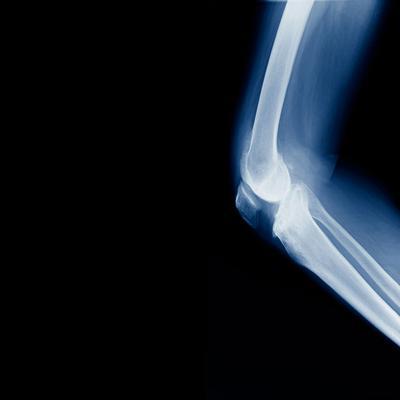

第三、痛风一般产生在脚关节,之所以出现在脚上,是因为人的脚是血液循环最低的部位,这样很容易导致脚痛、红肿和热痛。因此,痛风脚关节痛发生后,如果疼痛感严重,应该把脚放在冰桶里冷敷,以缓解疼痛感。